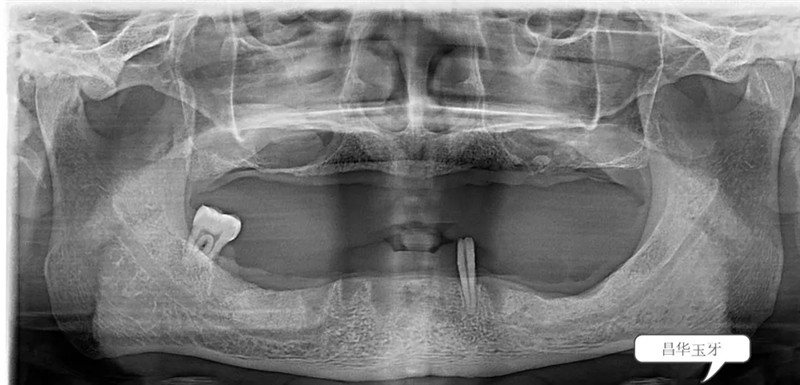

無論是直接的口腔檢查還是從全景片上來看,這位患者全口牙列所剩無幾,患者自述過程中亦可聽出患者是飽受無牙之苦。也確實(shí),從面容到進(jìn)食再到發(fā)音均受牙齒缺失的影響。(如下圖)